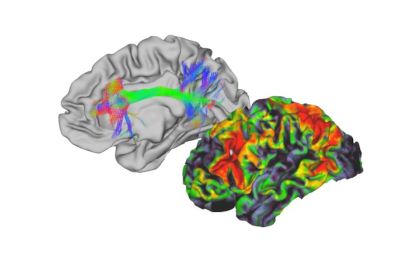

In a new study, published in Human Brain Mapping, a group of scientists, led by Dr Marcus Kaiser from the School of Medicine at the University of Nottingham, looked at epilepsy patients undergoing surgery.